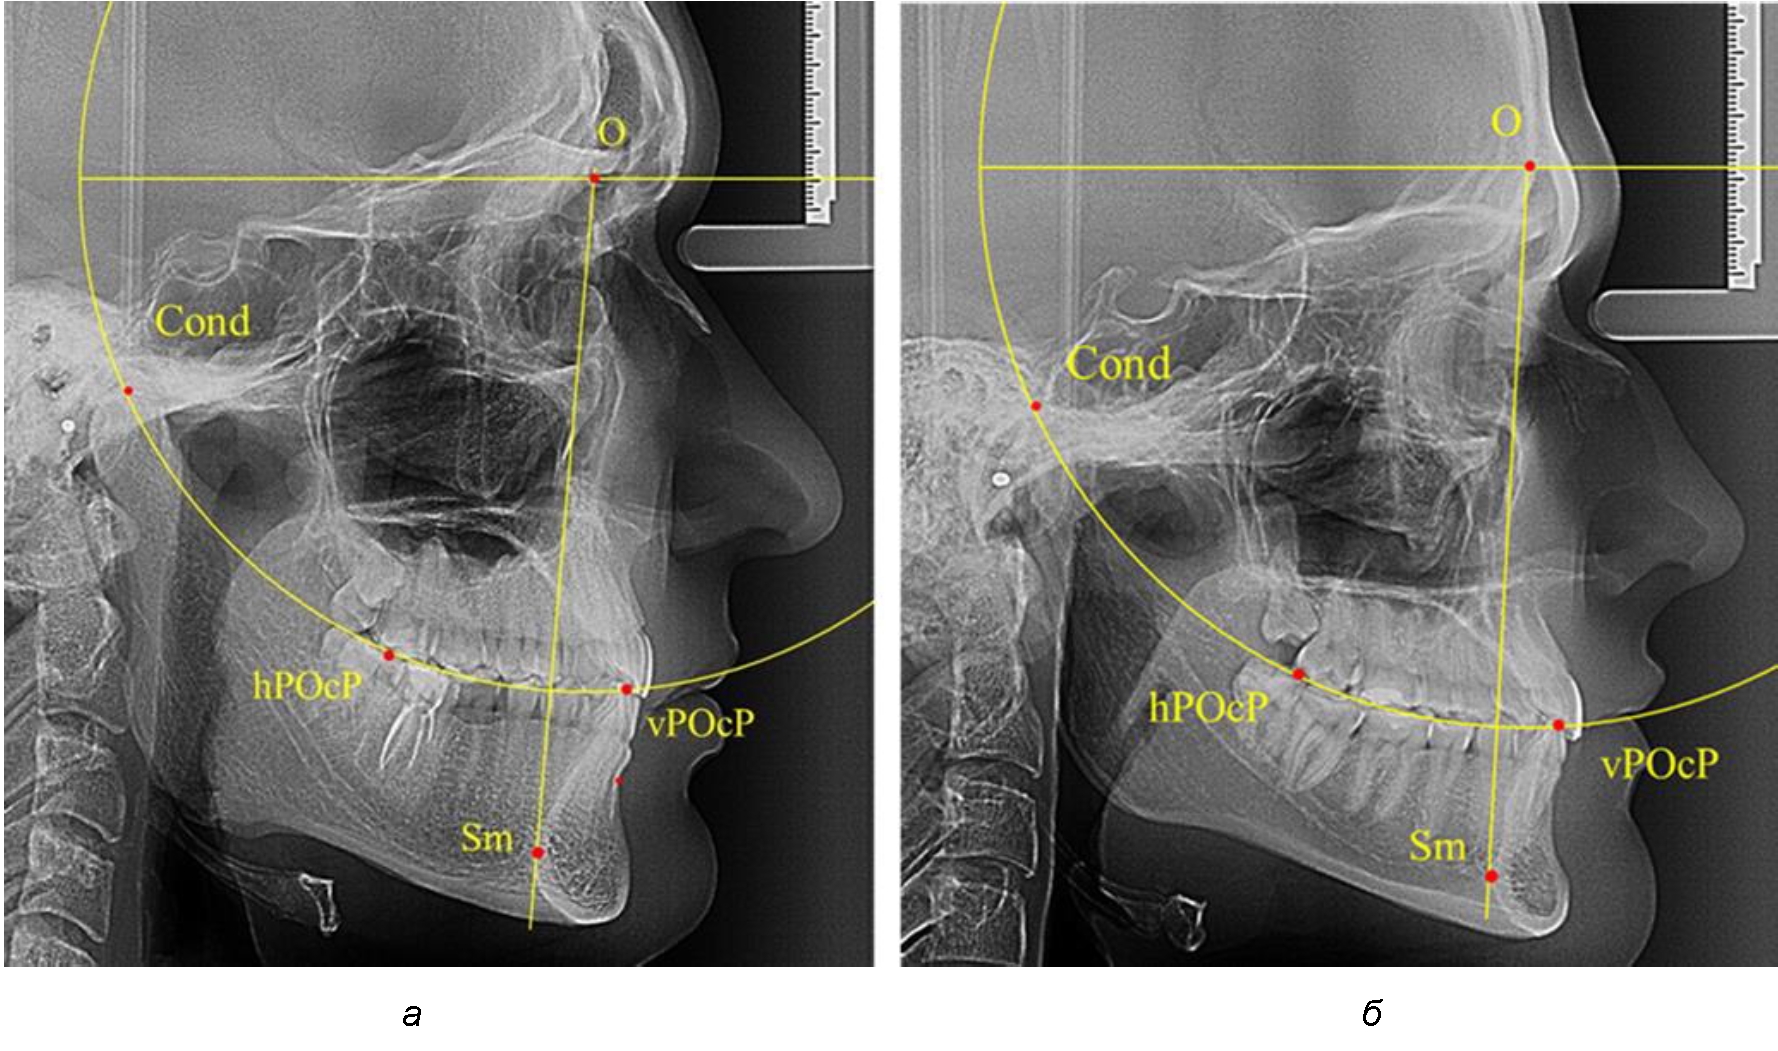

Анализ снимков проводили с использованием традиционного построения стресс-оси по Bimler. Для удобства построения использовали компьютерную программу PowerPoint. Основными точками для построения круга были передняя (vPOcP) и дистальная (hPOcP) окклюзионные точки, а также верхняя выпуклость суставной головки (Cond).

Вставка из программы в виде овала накладывалась на фотографию рентгенограммы и ручным способом растягивалась так, чтобы получился круг, проходящий через обозначенные реперные точки.

Центр окружности О, соединяющей точку резцового перекрытия с жевательной поверхностью зубов и серединой суставных головок, соединяли с выступающей точкой Sm на внутреннем контуре подбородка (рис. 1).

Рис. 1. Метод анализа ТРГ по Bimler

Результаты исследования рентгенограмм с мезотрузионным типом резцов показали, что линия Bimler проходила позади первых премоляров у людей с широким типом подбородочного выступа, однако окклюзия была физиологической и не требовала удаления премоляров, что носило рекомендательный характер при проведении подобных исследований при аномалиях прикуса. У людей со средними формами подбородочного выступа линия Bimler проходила впереди первых премоляров (рис. 2).

Аналогичная ситуация была у людей и с узкими вариантами подбородочного выступа.

Таким образом, при мезотрузионном типе зубочелюстных дуг расположение премоляра впереди линии Bimler при широких вариантах подбородка не может быть критерием выбора экстракционных методов лечения.

Рис. 2. Положение первых верхних премоляров при мезотрузии с широкими (а) и средними (б) размерами подбородка